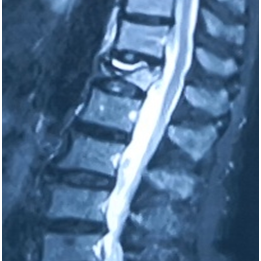

术前MRI

术后2周MRI